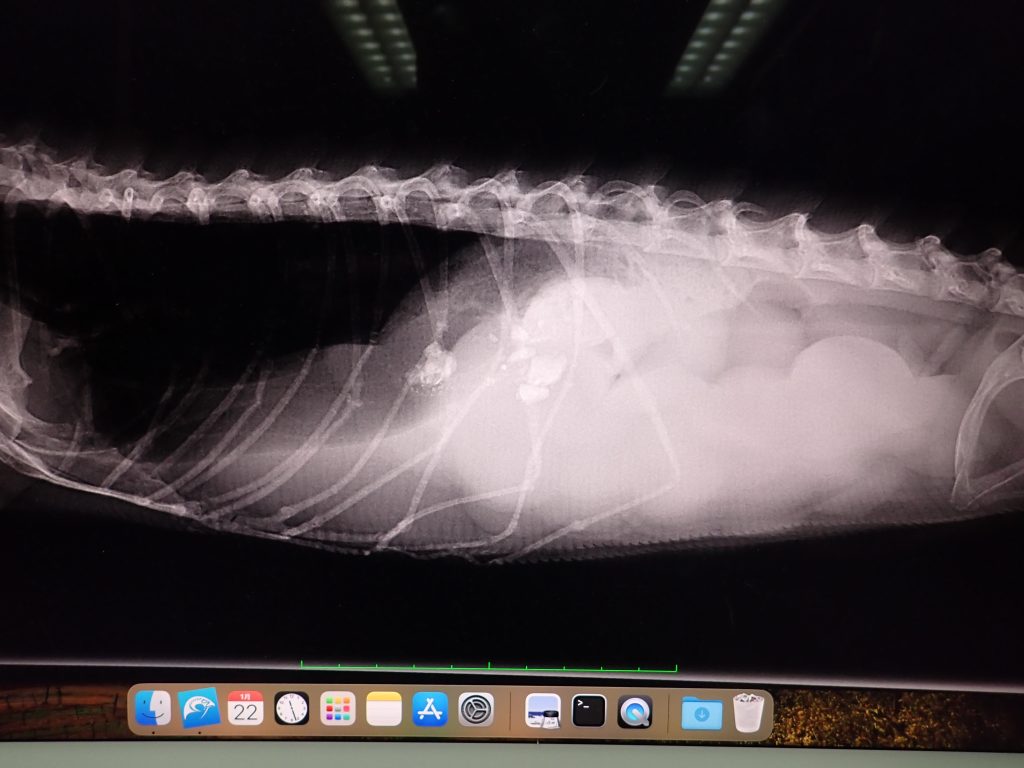

1ヶ月くらい食べが悪いという主訴

さぁ、あなたの診断は?

what is your diagnosis, this case ?

解答:腹内卵の疑い

ans.:intrauterine egg suspected